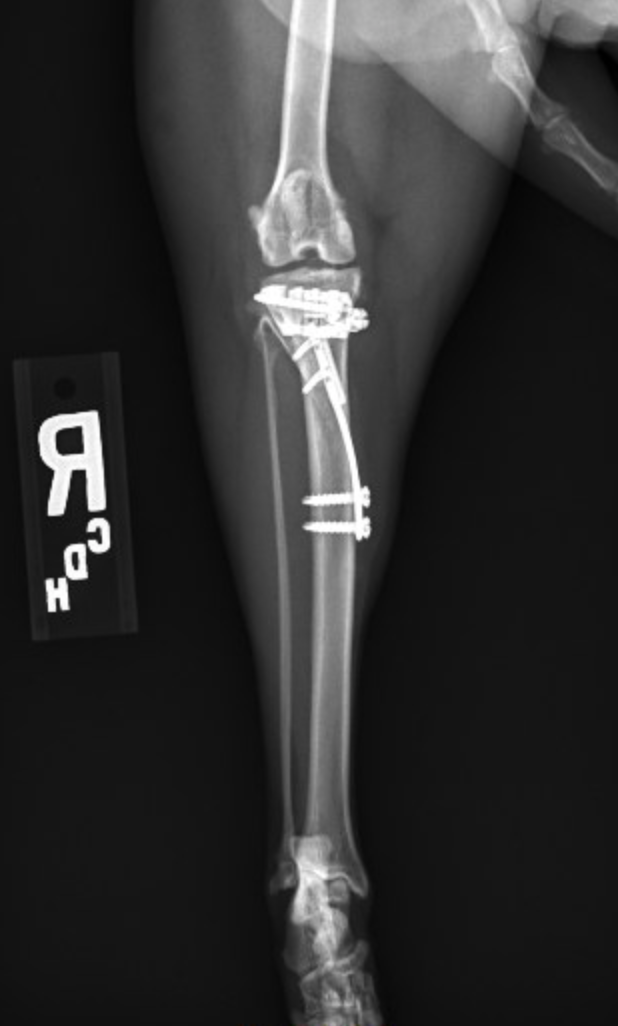

A TTTA surgery changes the biomechanics of the knee. The surgeon cuts into the tibia and alters the relative position of the two bone sections to create a 90-degree angle between the tibial plateau (the top of the tibia) and the straight patellar ligament, which inserts on the front of the tibia. This renders the stifle intrinsically stable, such that the function of the cranial cruciate ligament becomes redundant. It also treats the patellar luxation as the relative positions of the two pieces of bone can also be altered in another plane simultaneously to straighten the quadriceps mechanism. When the quadriceps mechanism is straight, there is no tendency for the patella to luxate. Minor adjustments to the technique and implants used in dogs were necessary to facilitate application in a cat, but Perry considered the surgery a success.

Sophie recovered well from anesthesia and was comfortably able to bear weight through her operated limb in less than 24 hours. Upon discharge, Sophie’s owners received strict instructions for incision care, activity limitations, physical rehabilitation, diet alterations and recheck appointments. For full recovery, Sophie needed strict exercise restriction to avoid complications such as implant breakage and slow bone healing.

“In the absence of any previous reports of this procedure being performed in cats, we could not entirely predict how quickly Sophie would recover. However, eight weeks post-op, her lameness improved rapidly with only a very mild and intermittent limp and her bone healed well with no complications,” Perry said. “Additionally, at follow-up exam, the instability previously noted affecting the right stifle had resolved and the patella could not be luxated.”